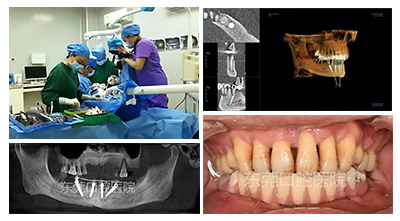

ALL-ON-4即刻负重种植技术

先进的ALL-ON-4即刻负重种植牙技术,仅需植入4颗种植体就能完成半口缺牙修复,并且可实现即拔即种,由于其种牙速度快,恢复周期短,非常受缺牙市民青睐。

ALL-ON-4即刻负重种植牙技术是为了解决无法种植的病例而诞生的,仅需植入4颗种植体(4颗种植牙根形成“W”状),获得颇具规模的骨接触面积,使受力均匀地分布到整体,所以牙根和烤瓷牙同时受力时,马上就感觉有嚼劲。

在东莞口腔医院接受ALL-ON-4半口种植牙手术,种牙速度快,半口即种即刻修复,当天戴牙。

东莞口腔医院王立超院长专注于口腔种植工作,十余年的口腔种植临床经验,成就了数千例种植修复病例。擅长全口牙齿缺失的种植牙修复、all-on-4全口即刻修复、牙周病的种植牙重建、微创种植、口腔美学修复等技术。

以下是院长ALL-ON-4半口种植案例:

白天种的牙,晚上就能吃东西,让缺牙市民轻松摆脱缺牙困境,不带伤口过好新年!